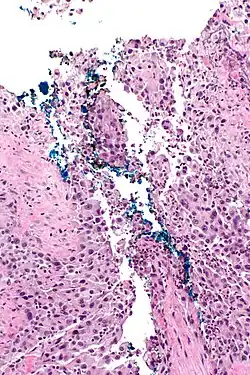

Jaja Schistosoma haematobium w błonie śluzowej pęcherza moczowego

Przywra krwi (Schistosoma haematobium) jest pasożytem występującym w Afryce Subsaharyjskiej i Bliskim Wschodzie, jej obecność jest związana ze zwiększonym ryzykiem raka płaskonabłonkowego pęcherza moczowego[1]. W cyklu życiowym przywry dochodzi do przebijania błony śluzowej pęcherza moczowego przez jaja pasożyta. Pasożyt stymuluje rozwój odpowiedzi zapalnej oraz procesów regeneracyjnych, a ostatecznie prowadzi do metaplazji błony śluzowej pęcherza moczowego[21]. Ponadto przywry sprzyjają przemianom azotanów i azotynów w rakotwórcze nitrozoaminy[22][23].

Endemiczne występowanie Schistosoma haematobium jest ściśle związane ze zwiększonym ryzykiem tego raka[24]. W regionach endemicznego występowania pasożyta rak pęcherza moczowego jest dominującym nowotworem złośliwym u ludzi. Przykładowo w Egipcie rak pęcherza moczowego łącznie stanowi ponad 30% nowotworów złośliwych, u mężczyzn jest najczęstszym nowotworem złośliwym, a u kobiet drugim po raku piersi[24][22]. W regionach endemicznego występowania przywry krwi dominującym typem histologicznym raka pęcherza moczowego jest rak płaskonabłonkowy, a nie rak urotelialny (przejściowokomórkowy)[24].